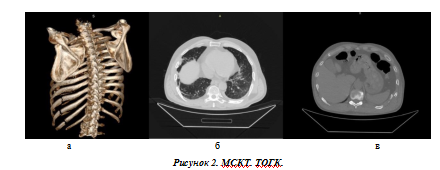

Тяжелая ТОГК. Мультипланарная 3D-peконструкция: поперечный перелом 6, 7, 8, 9, 10 —хребер слева по лопаточной линии, поперечный перелом тел 8, 9, 10ребер слева по средней подмышечной линии (а), аксиальный и фронтальные срезы: ушиб обоих легких, двухсторонний пневмоторакс, двухсторонний гемоторакс, подкожная эмфизема переднезаднебоковой поверхности грудной клетки с двух сторон (а, б).